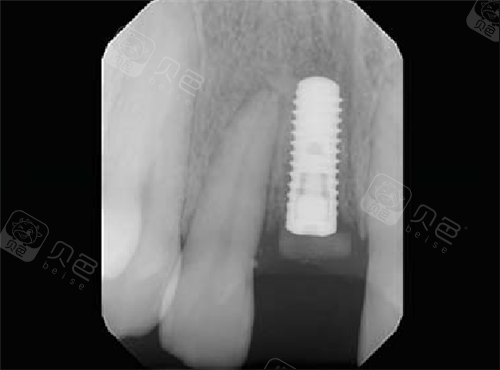

在植体长度上,普通种植体长度通常在八毫米至十四毫米之间,而穿颧种植体由于需要横跨上颌窦到达颧骨,其长度往往达到三十毫米至五十毫米。在手术难度上,普通种植属于基础外科,而穿颧穿翼则属于颌面外科的范畴,对医生的解剖学功底要求极高。

第三,稳定性极强。由于颧骨和翼突的骨密度极大,种植体的初期稳定性通常能达到四十牛厘米以上,远超普通牙槽骨种植的稳固程度。